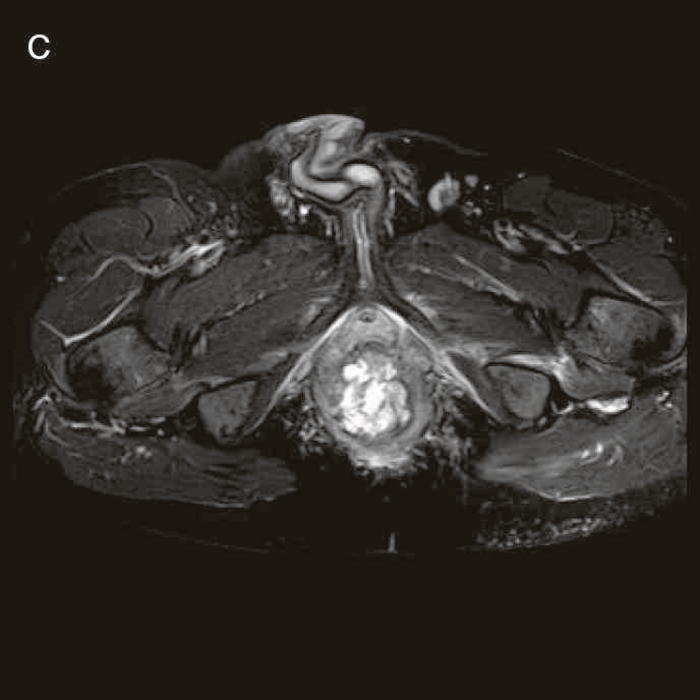

図27 CD直腸肛門部癌の骨盤造影MRI検査像

直腸内に増強効果を受ける分葉状の腫瘤を認める。